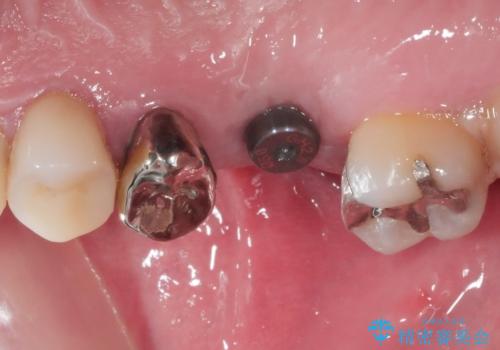

レントゲン等、検査を行ったところ骨の厚みは問題ないですが、

高さは少し低かったので、幅が太い短いインプラントを使って治療を行う計画を立てました。

インプラント治療により問題無く奥歯で噛めるようになりましたが、奥歯の噛み合わせが強いためインプラント周囲の骨吸収や他の歯の破折等が起きる可能性があります。

夜間就寝時のマウスピース装着、定期的なメンテナンスでレントゲン、噛み合わせの確認は必須です。